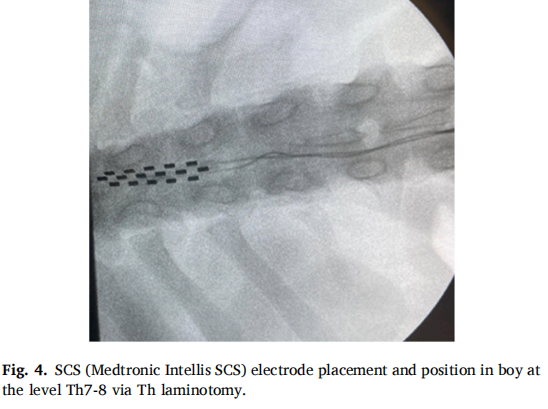

本研究采用 SCS硬膜外電極植入。病例1(CRPS1女性患者)接受下肢電極經(jīng)皮植入T10水平,上肢電極通過(guò)右側(cè)C6-C7椎間盤(pán)切除術(shù)放置;病例2(CIDP男性患者)通過(guò)T8椎板切開(kāi)術(shù)在T7-8水平植入電極。兩例均在全身麻醉下完成手術(shù),避免使用神經(jīng)肌肉阻滯劑以保留運(yùn)動(dòng)信號(hào)監(jiān)測(cè)能力。植入后設(shè)置10天試驗(yàn)期評(píng)估療效,確認(rèn)有效后植入永久脈沖發(fā)生器。術(shù)中采用透視引導(dǎo)確保精準(zhǔn)定位,術(shù)后定期調(diào)整刺激參數(shù)以?xún)?yōu)化治療效果。病例2因腦脊液泄漏經(jīng)歷三次電極位置調(diào)整,最終更換為椎板切開(kāi)術(shù)植入新電極。 圖5